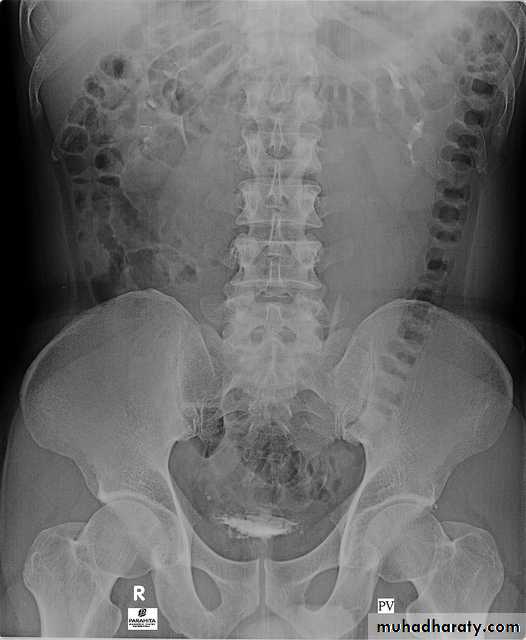

6. Post voiding full length film

Urinary system

4. Bladder

The bladder is a centrally located structure.

Smooth in outline.

Smooth indentation from above by uterus on the right or sigmoid colon on the left and from below by muscles of the pelvic floor is normal.

Other than that, any filling defect, wall irregularity or diverticula must be carefully looked for.